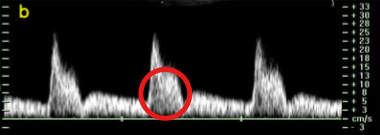

What is the name of this circled finding on the spectral waveform?

Spectral broadening

Which aspect of the spectral line represents the widening of the spectral line and filling of the spectral window?

Describe how spectral broadening appears on a spectral waveform? (2)

Widening of the spectral line

Filling of the spectral window